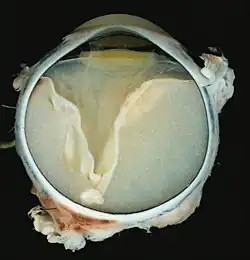

Grossly, retinal detachment and yellowish subretinal exudate containing cholesterol crystals are commonly seen.

Microscopically, the wall of retinal vessels may be thickened in some cases, while in other cases the wall may be thinned with irregular dilatation of the lumen.[11] The subretinal exudate consists of cholesterol crystals, macrophages laden with cholesterol and pigment, erythrocytes, and hemosiderin.[12] A granulomatous reaction, induced by the exudate, may be seen with the retina.[13] Portions of the retina may develop gliosis as a response to injury.